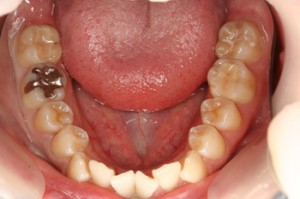

■口の中の金属を白くする症例

初診時